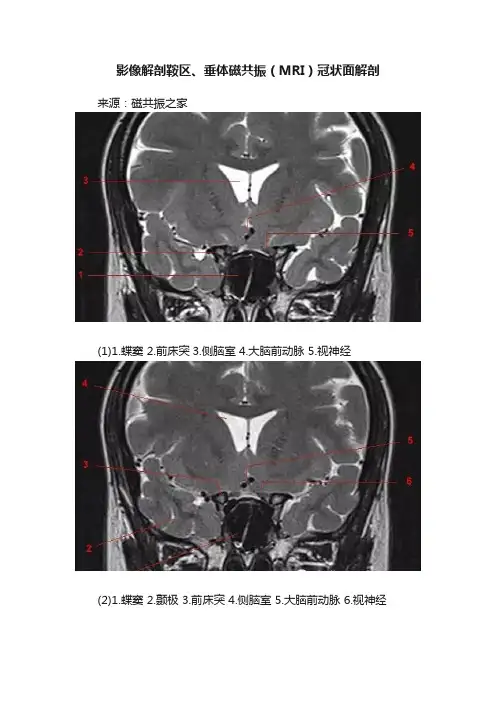

影像解剖鞍区、垂体磁共振(MRI)冠状面解剖来源:磁共振之家

(1)1.蝶窦 2.前床突3.侧脑室 4.大脑前动脉 5.视神经

(2)1.蝶窦 2.颞极 3.前床突 4.侧脑室 5.大脑前动脉 6.视神经